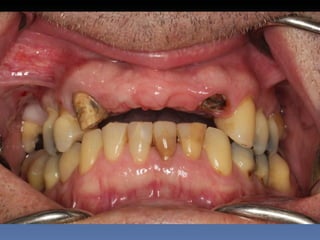

BOX 4

Eusébio Moreno

Idade – 73 anos

Sexo – Masculino

Raça – Caucasiana

ASA – II

Data- 23-04-2012

Diagnóstico: Desdentado parcial

bilateral posterior da maxila.

Plano de tratamento: Reabilitação posterior maxilar

esquerda, com instalação de 3 implantes endo-ósseos

(2.4,.2.5.2.6.), para reabilitação protética fixa.